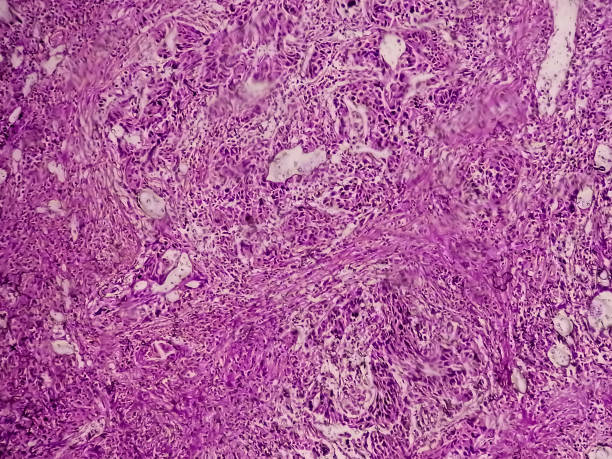

방광암은 방광 내부에 악성 종양이 생긴 것을 말합니다. 이 종양은 방광 벽에서 시작하여 방광 내부로 침입할 수 있으며, 심각한 경우 다른 조직이나 기관에도 전이될 수 있습니다.